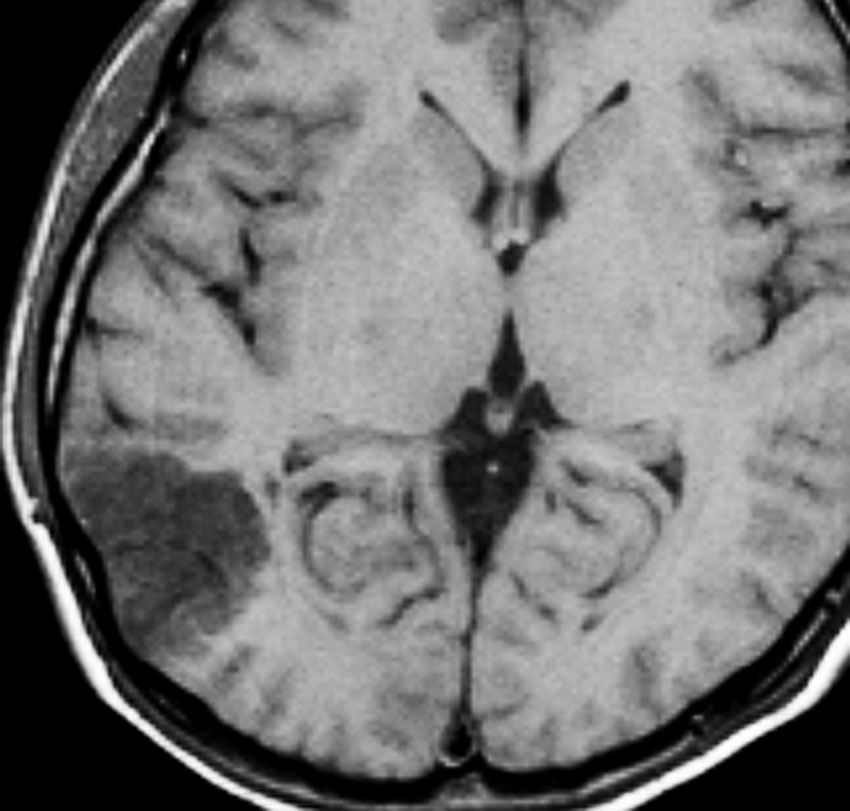

3歳で最初のてんかんらしいと言われる発作があり,その後は発作は見えず自動症と診断され徐々に学習能力の低下が認められ,7歳の時に外来を訪れました。週に3回くらい腹痛や嘔気があってすぐに眠くなってしまう。耳鳴がすごくてしばらく何も聞こえなくなってしまう,話も理解できなくなるなど,側頭葉てんかんの特徴をたくさんエピソードとして持っていましたが,症候性てんかんとは診断されませでした。側頭葉にどのような機能があるのかを証明してくれる症例でもあります。

典型的なDNTの画像で説明するまでもありません。ガドリニウムでは全く増強されませんでした。左上側頭回と角回の境界域に存在します。